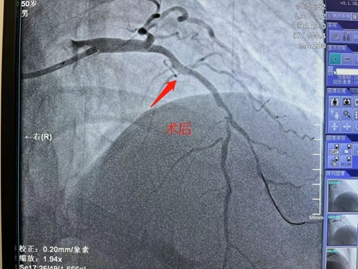

3月20日,是值得纪念的日子,商城县人民医院心血管内科心脏介入团队在郑州大学第一附属医院专家的指导下,顺利完成了6台高难心脏介入手术治疗,打破了我院开展PCI项目以来的单日最大量纪录,在我院心脏介入技术发展过程中具备里程碑式意义。 据心血管内科熊晨晖主任介绍,当日共有7人接受手术,其中6人分别完成了疑难复杂的支架植入和药物球囊治疗,术后血流再通良好,患者及家属对治疗效果均非常满意。 在北京安贞医院马长生教授团队的帮扶下建立的国家标准化心血管疾病中心,驻扎式派出叶益聪教授等专家的带教下及郑大一附院,郑大二附院知名专家的指导下,商城县人民医院心血管内科于稳中求进,不断探索学习,自2018年10月至今,已成功地完成支架植入治疗近600例,造福商城县广大心血管疾病患者。 一台台介入手术的圆满完成,一位位患者因及时救治而重获新生,无不体现着商城县人民医院心脏介入团队日益精进的诊疗技术,也显示出我院在介入治疗领域已具备较强的综合实力。时间就是生命,时间就是心肌,与时间赛跑,与死神搏斗!商城县人民医院心血管内科团队将会不懈努力,不断进取,为广大心血管疾病患者的健康保驾护航! 就医地址: 冠心病监护病房(CCU):2号病房楼4楼。 咨询电话:0376—7975373; 心血管内科病区:2号病房楼4楼。 咨询电话:0376—7973137